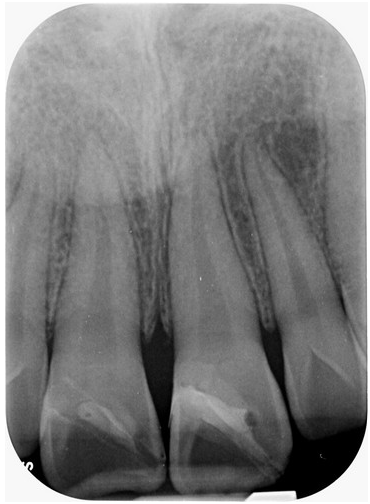

右圖:7歲孩童小松是在一年半前不小心把上顎新萌發的恆齒撞斷,圖為術前X光影像。(賴博堂提供)

7歲孩童小松是在一年半前不小心把上顎新萌發的恆齒撞斷,經急診醫師會診根管治療科賴博堂主任接手以活髓治療。現在的小松雖然偶爾會因咬到堅硬的食物而使黏上去的斷片掉落,需再重新黏上之外,整顆牙仍保留恆齒成長潛能。

另外,年輕恆齒斷裂後,根尖腫起來,即是牙髓發炎;這時就要看感染程度與牙髓殘存的活性,賴博堂主任表示,若牙髓發炎侷限在牙根管的中、上段時,還是能嘗試活髓治療;若牙髓已壞死至牙根中段以下,就要評估牙髓再生術式。